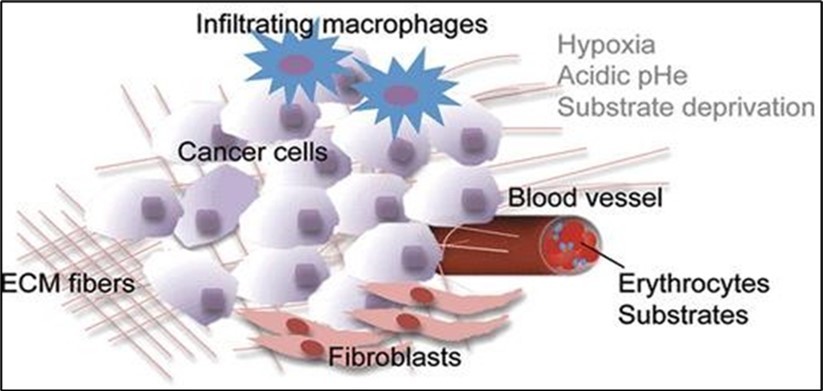

It is a non–invasive method. It can be used to monitor the chemical changes of tissues. We can simultaneously evaluate several metabolites. Two examples of where MRS is very helpful in the brain: The invasion of the tumor (Glioblastoma multiform (GBM) into the surrounding tissues, which is not clear in normal T2 images, but can be determined by MRS. By MRS, it is possible to distinguish two types of lesions that look similar to each other in normal MRI images (such as tumor recurrence and tumor necrosis after radiotherapy). MRS imaging has found wide applications in the field of cancer diagnosis. Among the fields of clinical application of MRS, we can mention the diagnosis (between normal and cancerous tissue, different types of cancer and neoplastic from non–neoplastic), designing the best treatment regimens for each patient, and monitoring the patient after treatment. MRS in tumors: In brain tumors, spectroscopy can determine the degree of malignancy. As malignancy increases, NAA and creatine decrease and choline, lactate and fat increase. Fat is seen in the necrotic parts of the tumor. Lactate concentration increases in rapidly growing tumors due to anaerobic glycolysis. Diagnosing tumor recurrence from the effects of radiotherapy: Increased choline is a marker for tumor recurrence. Changes due to radiotherapy usually decrease NAA, creatine and choline. If necrosis has occurred as a result of radiotherapy, fat and lactate can also be seen in the spectrum. Molecular imaging using spectroscopy Cerebral ischemia and infarction: When the brain suffers from ischemia, anaerobic respiration of glucose is used and lactate increases. Choline increases and NAA and creatine decrease. If it happens after ischemia, the fat signal is also seen. trauma: It is a useful method to assess the degree of nerve damage and predict the results. The clinical consequences are opposite to the NAA/Cr ratio, and the observation of lactate and fat indicates the seriousness of the condition. infectious diseases: decrease naa Inside the abscess, lactate, alanine, cytosolic acid and acetate increase. Alzheimer: In the advanced stages of Alzheimer's, NAA decreases and myo–inositol increases. MS: The increase of choline and lactate has shown that the increase of choline can be due to the increase of phospholipid as a result of breaking the myelin of the cell and the increase of lactate is due to the increase of the anaerobic respiration of the cell due to the increase of the cell metabolism. In addition, there is evidence of increased lipids, and most importantly, decreased NAA, which is caused by nerve damage. And recently, it has been found that glutamate and myoinositol levels increase in acute MS lesions. Parkinson: In most studies in Parkinson's disease, no changes in metabolites have been observed, only when Parkinson's has caused brain atrophy, a decrease in NAA in the basal ganglia has been observed (Figure 3, Figure 4, Figure 5, Figure 6).

Figure 4.Infiltrating macrophages of cancer cells in interaction with hypoxia acidic pHe substrate deprivation.